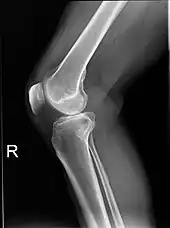

X-ray

Knee X-ray